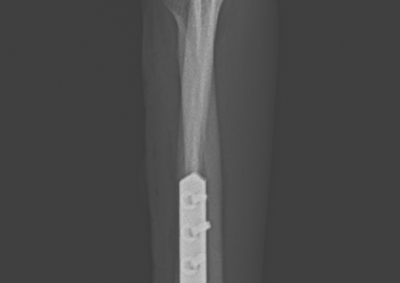

整形外科 注意 ボタンをクリックした先に、治療中および手術中の画像が説明で使用されている場合がございます。 そのような画像に弱い方は閲覧なさらないようお願いいたします。 整形外科 上腕骨外顆骨折の癒合不全 整形外科 大腿骨遠位開放および粉砕骨折 整形外科 膝蓋骨内方脱臼+前十字靭帯断裂 PGR#21+CBLO #251 整形外科 犬の前十字靭帯断裂に対するCBLO #250 整形外科 脛骨粉砕骨折 整形外科 内側鉤状突起分離症(Fragmented Medial Coronoid Process:F... 整形外科 股関節全置換術(トータル・ヒップ・リプレイスメント)#27 整形外科 橈骨固定術 #268 整形外科 橈骨固定術 #267 整形外科 橈骨固定術 #266 整形外科 股関節脱臼に対するBUSTOR #67 整形外科 脛骨粗面剥離骨折 <1234567> 症例カテゴリー 放射線治療整形外科軟部組織外科脳神経外科内科腫瘍外科救急・集中治療リハビリテーション科腫瘍内科内視鏡科脳神経科呼吸器外科中医・漢方猫の腎移植循環器科